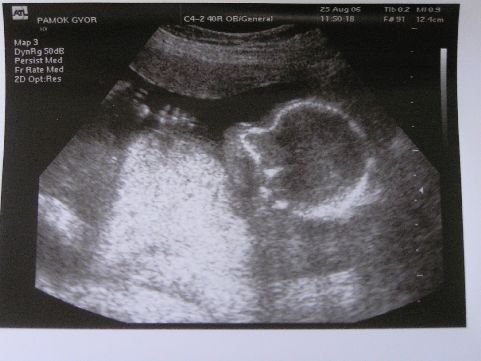

Jól értem, hogy kisfiút vársz? Készült kép? Ha igen, tedd fel kérlek!

Kép

Örülök, hogy mégsem nyíltál ki. Van képed amit feltehetsz?Ja és igen kisfiú, akkor bekékezlek:)

Havtünde! :) Csak nem pöcsös???? :lol: :lol: És nagyon édes :)